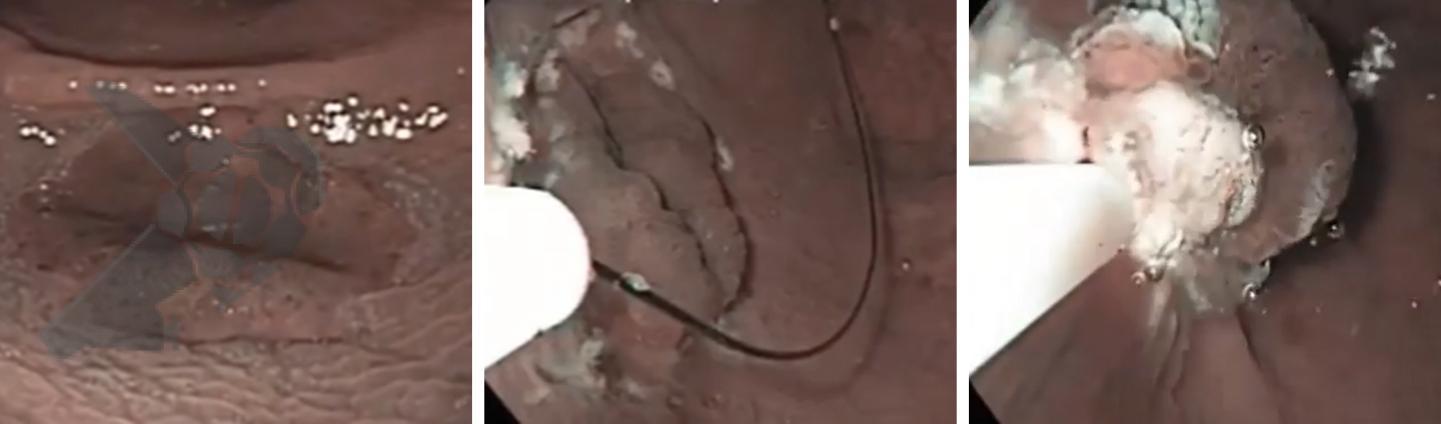

Figura 2. Mucosectomía underwater. Lesión plana del recto. Infusión de agua seguida de captura de la lesión con asa, sin inyección.